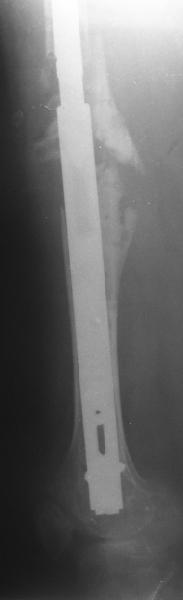

Female, rheumatoid, THA in 2003, car accident in 2006, failed plating. Nailing in Oct 2007. The nail is solid with hollow proximal part where the stem is docked. Last images are in 1 year after

nailing.